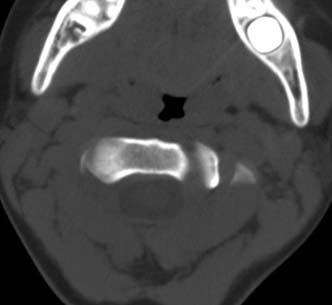

患者在校与同龄孩子打闹后(据家长说被拳击中颈部)出现颈部不适30分钟后入院检查,来时脖子歪斜。请大家看看枢椎齿状突及寰枢关节有问题吗?(3mm层厚断层扫描)。